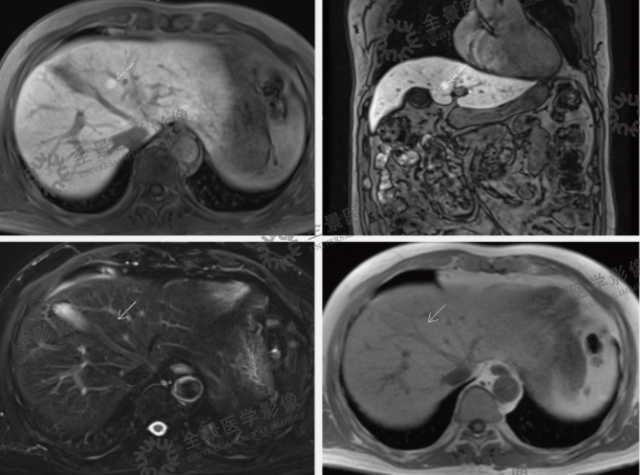

案例:中老年男性,体检发现肝占位,左叶内侧段小结节,约 10 mm 左右,当地普外科考虑小肝癌,建议手术治疗。为明确诊断来我中心。进行 MRI 普美显增强扫描肝脏大小、形态正常,肝表面光滑,左右叶比例协调,肝裂不宽;肝左叶内侧段见一类隋圆形结节影,长径约 10 mm,T1WI 呈等低信号,T2WI 呈等稍高信号,DWI 呈稍高信号,增强扫描肝动脉期明显强化,门静脉期及延迟期呈稍高信号,肝胆期呈高信号。

结论:肝脏左叶内侧段结节,诊断:肝脏局灶性结节增生(FNH)。